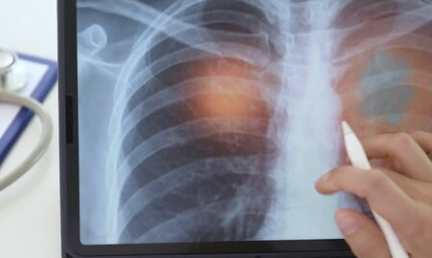

COPD 진단 방법: 숨차다고 모두 COPD는 아니다

COPD는 특정 증상만으로 진단되는 것이 아니라, 폐 기능 검사(Spirometry)를 통해 폐활량과 기류 제한 정도를 객관적으로 확인해야 합니다.

주요 진단 절차

- 폐기능 검사(FEV1/FVC 비율 확인)

- 흉부 X-ray 또는 CT

- 기침·가래·호흡곤란 기간 확인

- 흡연력·환경 노출력 조사

천식과 구별하는 것이 특히 중요한데, 천식은 약물 반응이 더 좋고 가역성이 크지만, COPD는 구조적 손상으로 인해 회복이 거의 어렵습니다.